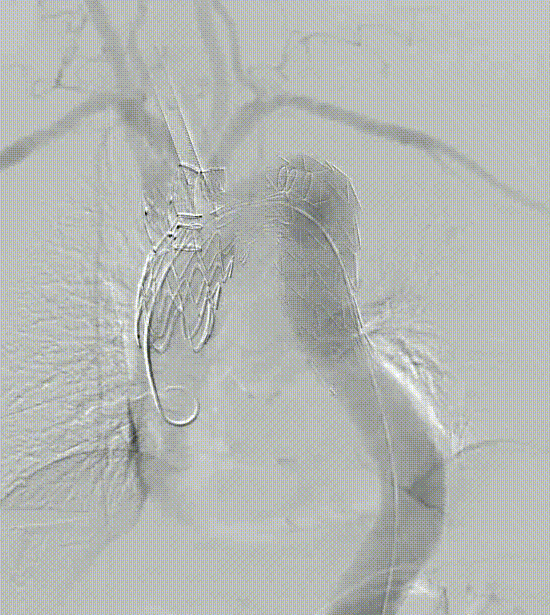

★ 病例2:主动脉弓动脉瘤III型弓

III型弓,血管扭曲,LSA与主动脉呈锐角

术后造影无内漏,各分支形态良好,血流通畅